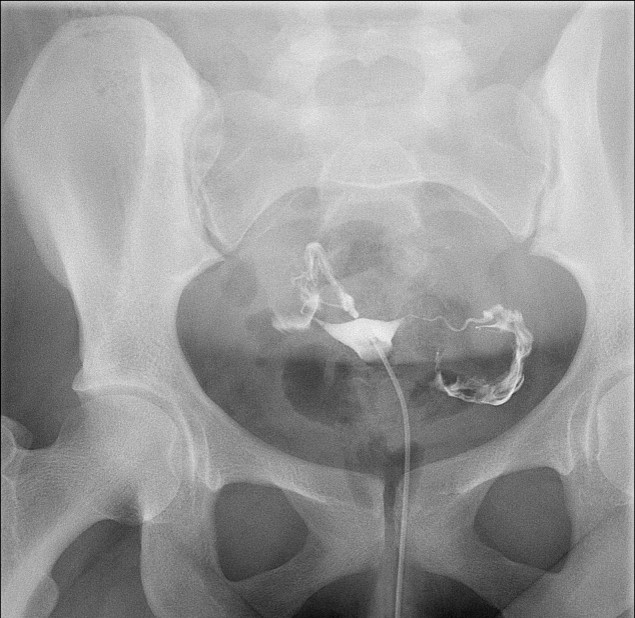

- When reviewing the preliminary scout film, you should see multiple surgical chain sutures in the pelvis

(key image 31)

(key image 32).

- As you instill contrast material into the J pouch, obtain images of the pouch and ileoanal anastomosis fully distended with contrast material in each of the following four (4) positions:

- left lateral

(key image 34)

- left posterior oblique

(key image 35)

- supine (AP)

(key image 36)

- right posterior oblique

(key image 37).